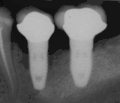

В дальнейшем обязателен ежегодный осмотр специалистом, в процессе которого:

- с помощью рентгенографии изучаются качество и плотность костной ткани;

Под термином «имплантация зубов» в стоматологии понимают только вживление зубного имплантата. В дальнейшем на вживлённый имплантат с помощью цемента крепится коронка, которая может быть временной — пластмассовой, металлокерамической, керамической, золотой и т. д. Относительно кости она должна располагаться на том же уровне, на котором ранее располагалась коронка зуба, замещаемого имплантатом. В практике чаще всего применяются два вида фиксации коронок на имплантаты: цементная или винтовая.